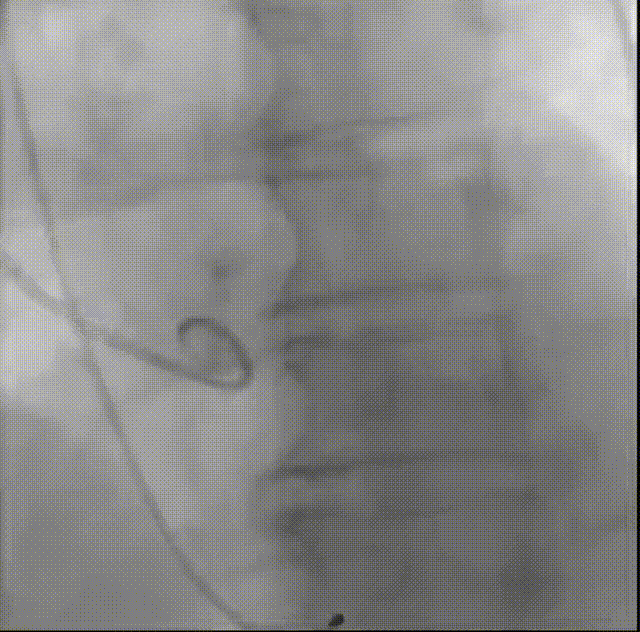

罗建方教授 广东省人民医院(点击查看专家详细简历) 设计本为临床需,耐久守护好芳华:任何医疗产品的设计初衷与最终归宿,都应落在 “临床获益” 这一核心上。尤其在 TAVR 领域,年轻患者预期寿命长,术后瓣膜的长期性能直接关乎其生活质量与生存预后。瓣膜耐久性问题,是落到临床实践中亟待突破的关键课题。传统瓣膜在长期使用中,可能因结构老化、功能退化等问题,难以满足年轻群体数十年的健康需求,二次手术风险也随之攀升。因此,产品设计必须直面这一临床痛点:通过材料革新增强抗钙化性能及生物相容性,以技术突破延长瓣膜有效使用寿命。此次临床应用的预装干瓣Prostyle A®是TAVR领域的革新理念,干瓣预期会为临床提供更耐久性的保障,实现了与临床需求的精准对接,为年轻群体的瓣膜治疗提供更坚实的保障。 李捷教授 广东省人民医院(点击查看专家详细简历) 干瓣技术求革新,性能兼顾护临床:干瓣的技术革新在创新的同时需要和临床实际需求深度耦合,兼顾TAVR术中的核心考量点。临床操作中,瓣膜能否顺利过弓,直接影响手术效率与安全性。Prostyle A®短瓣架设计及第二台阶的柔顺设计,术中操作丝滑;同时,瓣膜植入后的径向支撑力必须平衡得当,才能实现稳定锚定;释放后造影显示:瓣膜形态舒展,轻度瓣周漏,舒张压升高,冠脉开口未受影响;瓣周漏是影响术后效果的关键隐患,双层裙边设计通过多重密封机制降低反流风险,为患者长期获益筑牢防线。这些性能的协同优化,最终目的是让干瓣在临床中真正做到 “好用、耐用、安全用”,为患者预后提升提供坚实支撑。 患者病史 患者因 “活动后气促伴头晕 2 月” 入院。 现病史:2月前无诱因出现活动后气促,休息后缓解,伴头晕,夜间阵发性呼吸困难。超声检查发现:主动脉瓣重度狭窄并重度返流(跨瓣流速 4.3m/s,峰值压差 73mmHg);主动脉 + 冠状动脉 CTA 提示主动脉瓣显著钙化,升主动脉及分支粥样硬化,冠状动脉轻度狭窄(RCA 狭窄 30-40%)。 既往史:高血压病史 15 年,规律服药,血压控制稳定。 术前诊断:非风湿性主动脉瓣狭窄伴关闭不全(重度)、心功能 II 级(NYHA)、高血压病 2 级(高危)、冠状动脉粥样硬化。 术前CT 三叶瓣,瓣叶增厚中度钙化,右无交界钙化粘连,瓣环径25.1mm,LVOT 25.1mm,直筒型结构;窦部空间足够,升主未见增宽,瓣环水平夹角55°;冠脉开口位置佳,无冠脉风险;入路散在钙化、外周双侧入路无明显迂曲,双侧内径可、中分叉,左右侧均能够支持20F 大鞘通过。 造影角度及入路 右窦居中位RAO 5° CAU 26° 左冠切线位LAO 11° CRA 12° 手术策略 右侧股动脉为主入路,左侧为辅助入路;使用20球囊预扩,准备AV26瓣膜,冲洗口朝向3点钟方向送入输送系统性能,初始定位真实瓣环0位释放,最终锚定约瓣下3mm,工作位评估瓣膜稳定性与冠脉情况。 手术过程 根部造影 20mm 球囊预扩无明显腰征 术中使用26号瓣膜,瓣膜释放贴边迅速 80% 工作位观察瓣膜位置良好 释放后造影显示:瓣膜形态舒展,轻度瓣周漏,舒张压由术前30mmHg升为 60mmHg,冠脉开口未受影响。 术后超声:跨瓣流速降至1.6m/s,平均压差降至5 mmHg,心功能显著改善。 Prostyle A®预装干瓣——助力临床最优化解决方案: 1. 抗钙化与耐久性:Micro-EX™专利技术提升瓣膜抗钙化能力,适配患者瓣叶中度钙化的解剖特点,为长期疗效提供保障。 2. 柔顺过弓与精准定位:短瓣架设计 + 远端超滑涂层,确保患者输送系统过弓顺畅;瓣架流入端微直筒设计,让定位贴边更迅速,减少了手术时间; 3. 80% 可回收设计:便于术中调整观察,减少起搏时间,从而减少并发症。 4. 简化手术流程:预装设计缩短操作时间,20F 大鞘兼容外周入路,降低血管损伤风险。